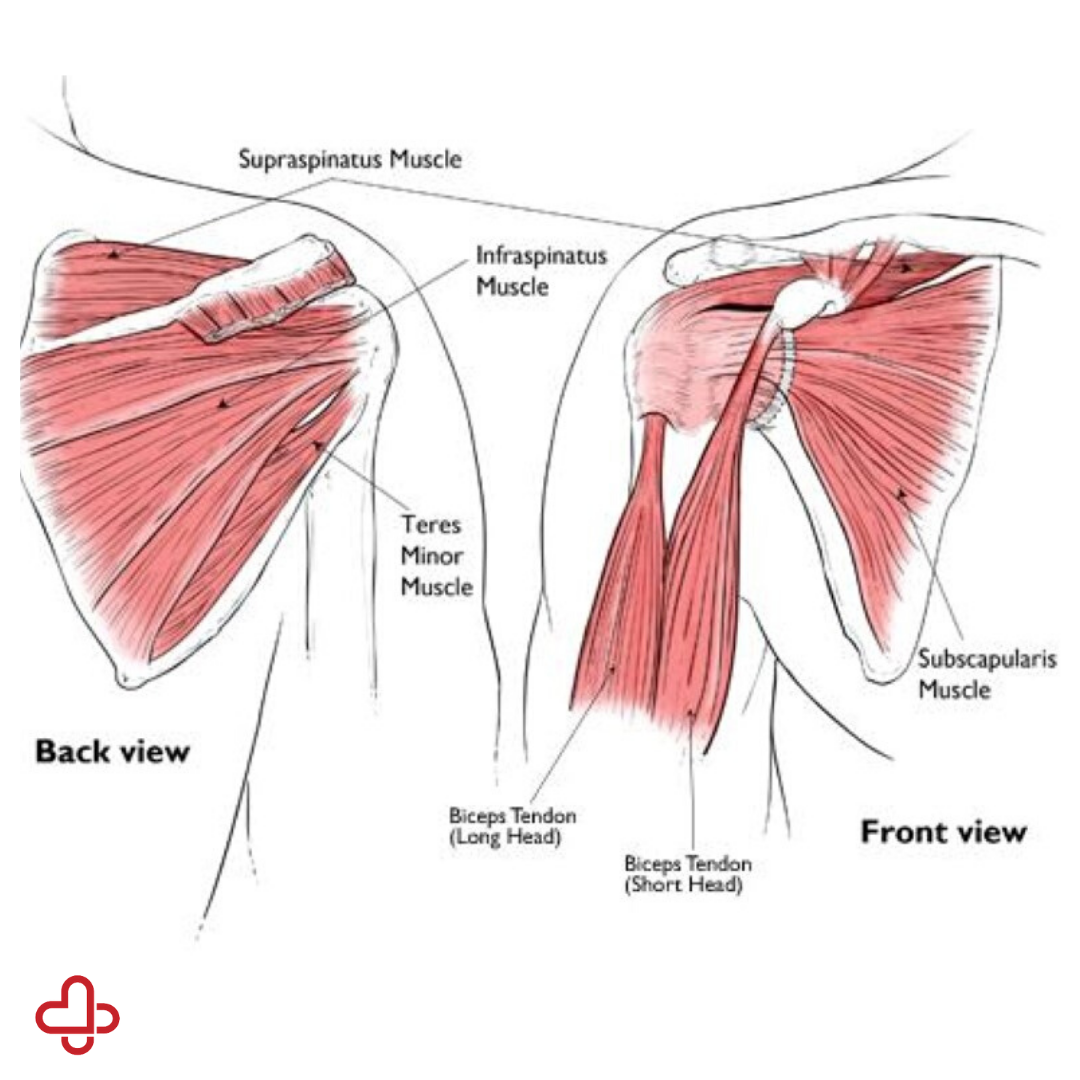

Фотографии мышц ротаторной манжеты плеча